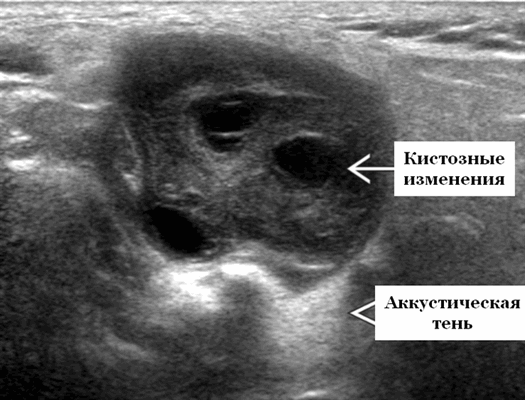

Важнейшее место в дифференциальной диагностике различных внеорганных опухолей шеи занимает ультразвуковое исследование. В В-режиме метастазы в лимфатические узлы имеют неоднородную структуру, капсулу толщиной до 2 мм, невриномы — изоэхогенную однородную структуру без выраженной капсулы, кисты - гипоэхогенную структуру с наличием мелкодисперсного жидкого содержимого и капсулу толщиной до 1.5 мм. Кровоток по сонным артериям характеризуется отсутствием локального повышения скорости, что свидетельствует о неизменности гемодинамики. В 30 % случаев определяют гемодинамически значимую компрессию яремной вены. Сосудистый рисунок неврином чаще представлен множеством сосудов, преимущественно артериями, диаметром до 2.2 мм с коллатеральным типом кровотока, в шванноме сосуды с венозным характером кровотока, внутри кист сосудистый рисунок не выражен.

Серошкалльное УЗИ. Четко выраженная опухоль от округлой до овальной формы. Гипоэхогенная по отношению к фоновой паренхиме околоушной железы. Часто присутствуют анэхогенные кистозные компоненты. Заднее акустическое усиление или через передачу часто присутствует даже в преимущественно солидных опухолях. Сужающиеся концы на границе раздела опухоль-нерв обычно не наблюдается, так как лицевой нерв обычно слишком мал, чтобы быть визуализированным на ультразвуковом сканировании, но если присутствует, настоятельно рекомендуется выставлять диагноз шванномы. Отсутствие сопутствующей шейной лимфаденопатии